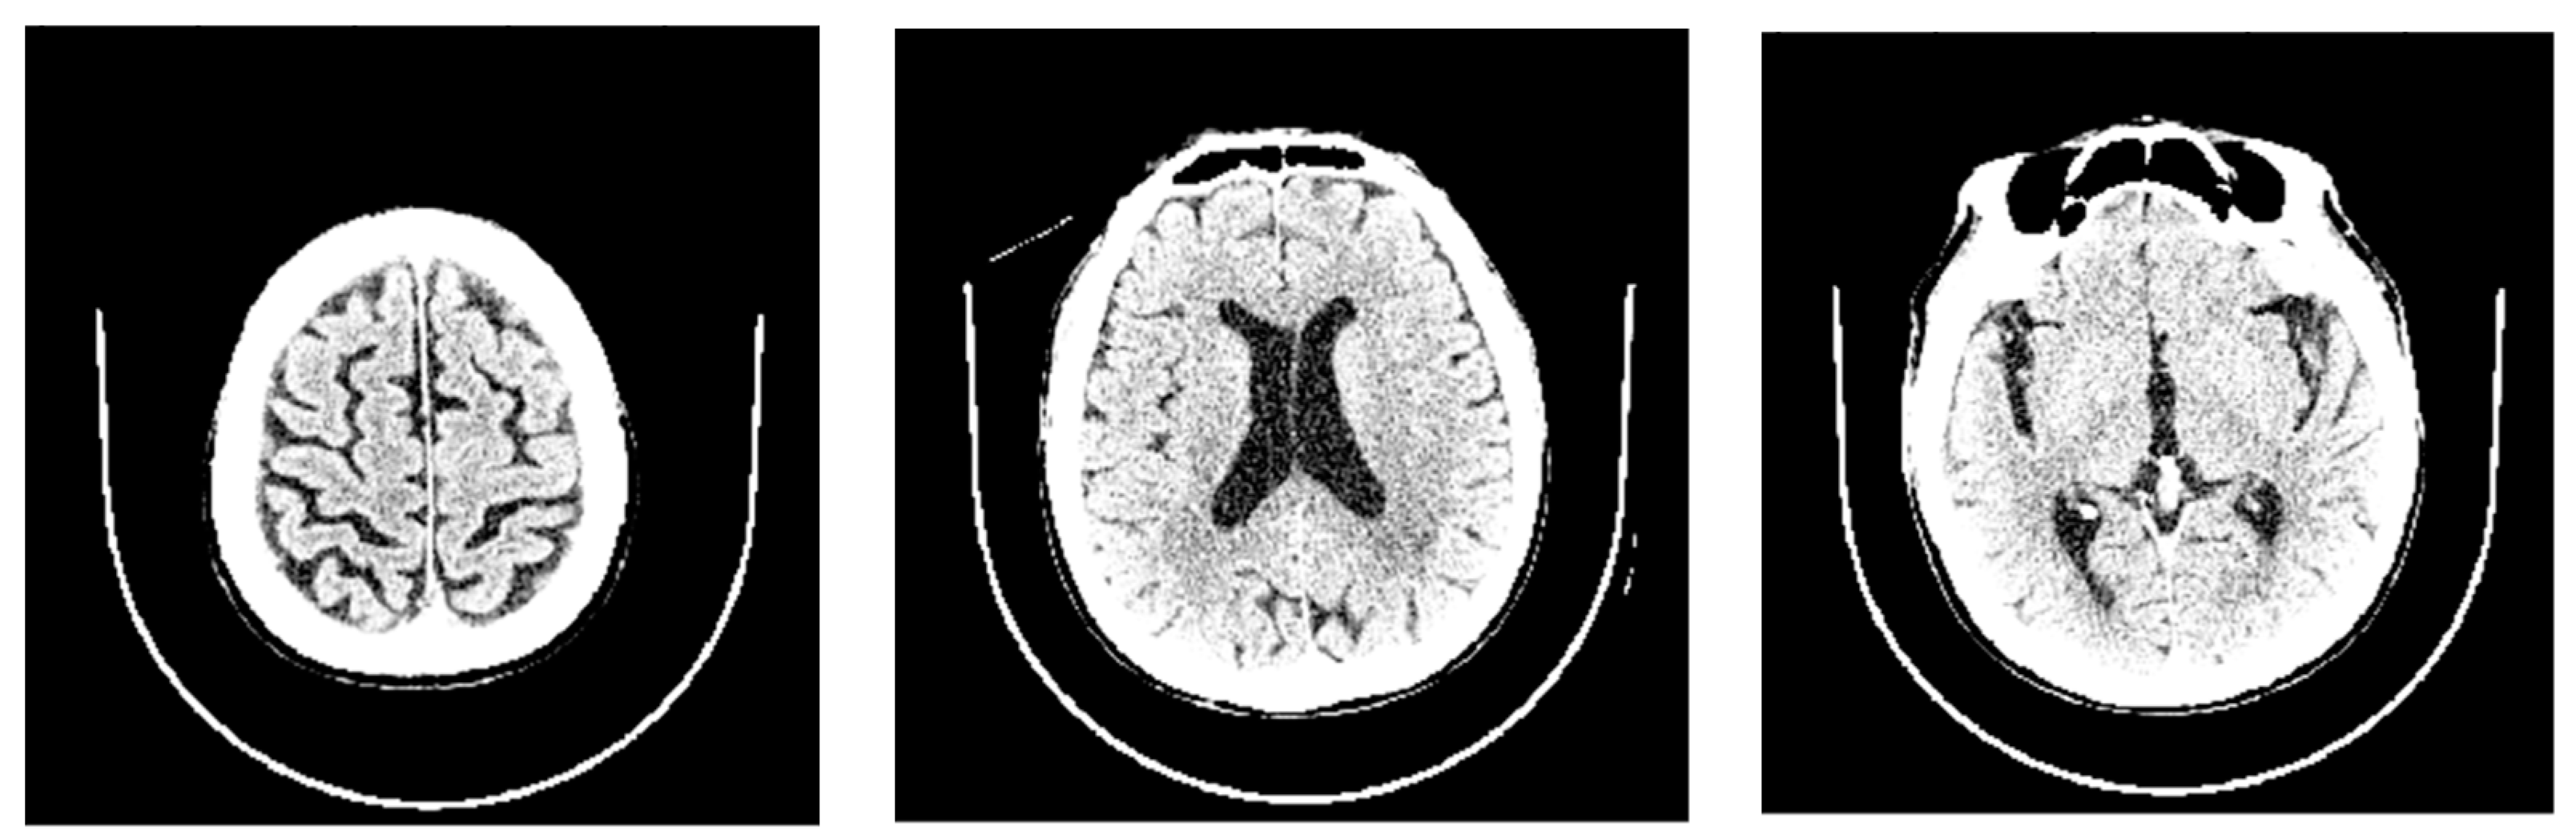

2.4. AI Evaluation